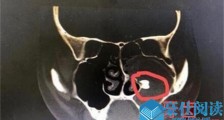

- 女孩鼻腔里长牙是怎么回事 揭秘女孩鼻腔里为什么会长了颗牙

- 一般来说,牙齿都是长在口腔里面的,但家住红安的17岁女孩小静(化名)的鼻腔里长牙,这令人费解,怎么回事?鼻腔里长牙齿的原因是什么?小静的情况如何?在接下来的内容中都可以揭秘了。据悉...